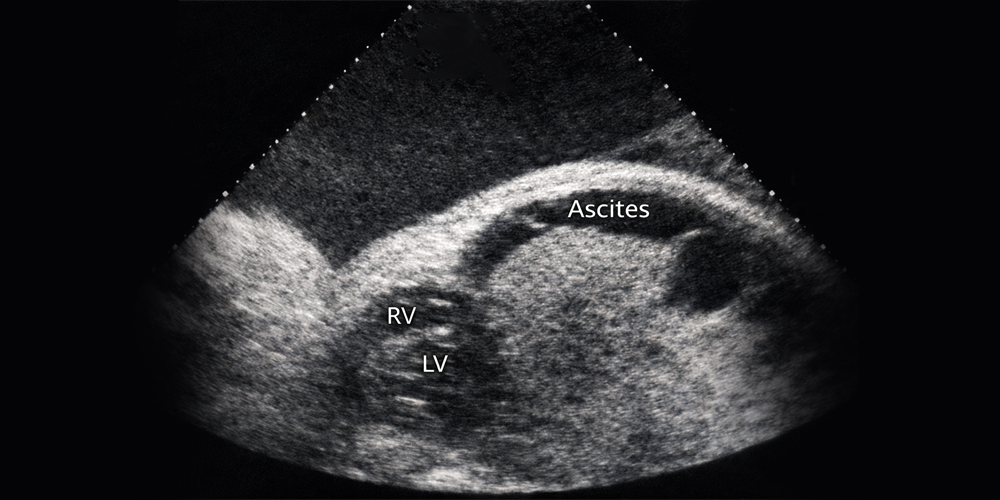

Bebeğin üç iç boşluğundan (karın, göğüs, kalp) en az ikisinde aşırı sıvı toplanması ve bu arada da ciltaltının da su toplaması sonucu bebeğin aşırı şişmesine hidrops fetalis adı verilir.

Non-immün hidrops ise, kan uyuşmazlığı olmadan bu durumun ortaya çıkmasıdır. Neden olabilecek hastalıkların uzun bir listesi vardır. Akademik amaçlı olarak neden araştırılabilir. Nadiren de bulunabilir. Ama doğrusunu isterseniz, sadece kalpte ritm bozukluğu durumlarında ritmi ilaçla düzeltebilirsek tedavi imkânı doğabiliyor. Onun dışındaki uzun listeden bulabildiğimiz nedenleri maalesef tedavi edemediğimiz için benim kendi kanaatimce bu araştırmaların hastalarımıza doğrudan bir yararı olmuyor.

Sonuçta hidrops aşamasına kadar gelmiş bir bebek için durumun çok ağır olduğunu söyleyebilirim.